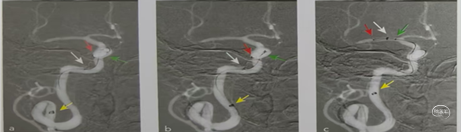

术中造影显示:Ⅲ型弓,左侧颈内C1段迂曲呈V型,C3段迂曲,C6段迂曲成环状,M1段闭塞,未向远端供血。

术前血管通路评估:Ⅲ型弓,左侧颈内C1段迂曲呈V型,C3段迂曲,C6段迂曲

成环状。

再次将支架置于M1远端,在支架铆定下跟进中间导管越过了C6迂曲到达M1段,抽拉结合2次取栓。通过中间导管进行二次抽吸后造影显示:血管再通,M1远端仍有小节段狭窄,但血流达到3级。结束手术。

建立通路和抽吸导管输送的插图。Nueron MAX长鞘开始应置于颈动脉360°环的近端,以避免发生颈动脉夹层(图1)。沿着微导丝-微导管-抽吸导管组成的三同轴系统,可使长鞘安全地沿360°环向远端推进,通过C1段环状迂曲部位,同时并不会强行改变这种血管迂曲的状态。随后在长鞘高到位支撑下容易将抽吸导管继续向M1段的血栓部位推进。下图。